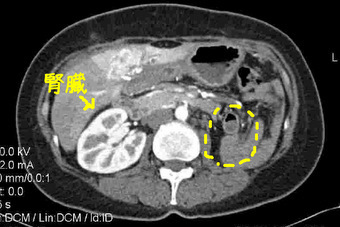

あと、こちらも教えてもらったのですが、向かって左に見えるのは私の右の腎臓。普通なら左にも同じものがあります。

ちなみに私は胆のうも脾臓もないし、膵臓も半分しか残ってないし、腸もかなり切り取ってます。

あと、こちらも教えてもらったのですが、向かって左に見えるのは私の右の腎臓。普通なら左にも同じものがあります。

ちなみに私は胆のうも脾臓もないし、膵臓も半分しか残ってないし、腸もかなり切り取ってます。